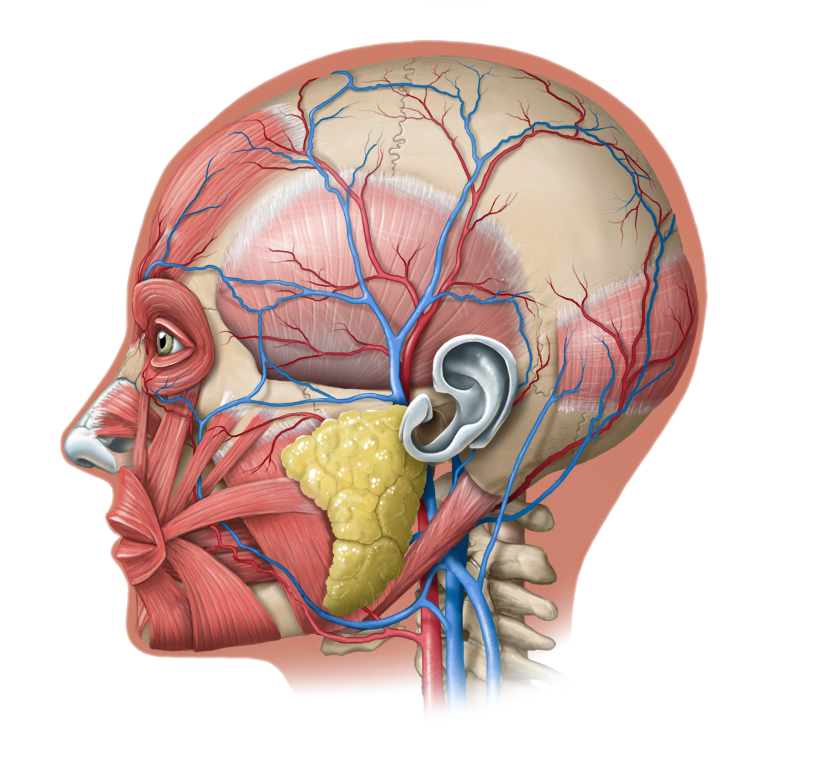

Medical Illustration

All images are works made for hire and are the exclusive property of the client. These are shown as sample purposes of my work only. For licensable work, please see my Illustration Services page.

Contract freelancer for many others, some examples of my work below.